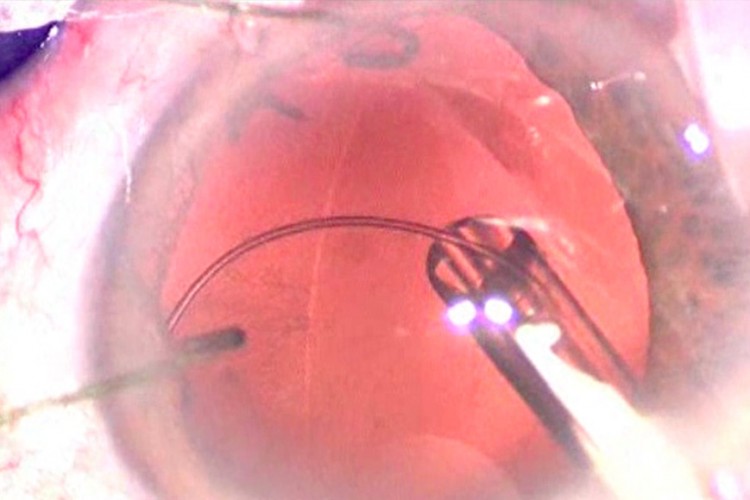

Greffe cornée Carlevale